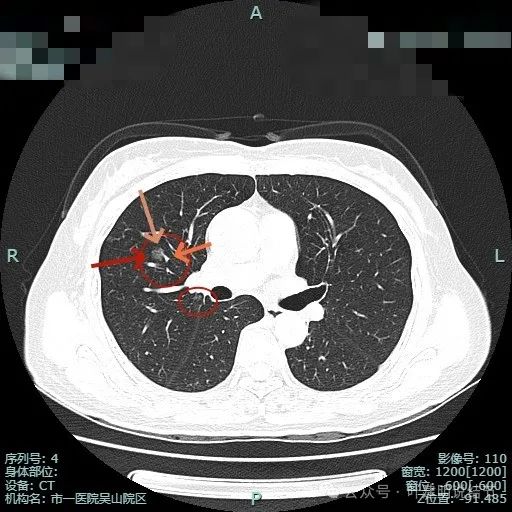

病灶1已经淡,且靠降主动脉近;病灶2密度其实也不纯,灶内有微小血管穿行,边缘侧有血管贴边,与支气管管壁间没有间隙。

病灶1边缘部分的样子;病灶表面欠光滑,有血管贴边。整体轮廓与边界清楚。

病灶2血管与病灶间没有间隙,表面浅分叶,并贴着斜裂。

斜裂略有牵拉向病灶,灶内密度稍不均,边缘有短细小毛刺征。

上叶前段有新的病灶出现(病灶3),也是磨玻璃密度,轮廓与边界清,有空泡征;病灶2密度不纯,轮廓较清,与斜裂没有间隙。